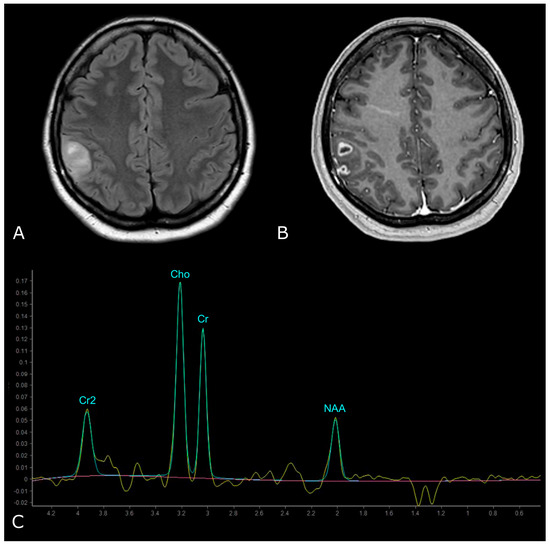

5. MR Spectroscopy

5.1. Principles of MR Spectroscopy, Metabolites and Their Function

5.2. MRS in Brain Tumors

5.2.1. Differentiating HGG from LGG

| Metabolites | Peaks | Biological Significance |

|---|---|---|

| N-Acetylaspartate (NAA) | 2.02 ppm | brain-specific molecule, marker for viable neurons (“neuronal marker”) |

| Choline (Cho) | 3.20 ppm | marker of tumor cell proliferation |

| Creatine (Cr) | 3.03 and 3.9 ppm | marker of energetic systems and intracellular metabolism |

| Lactate (Lac) | doublet peak at 1.33 ppm, inverted below the baseline at long-intermediate TE | marker of anaerobic metabolism |

| Lipids (Lip) | From 0.90 ppm to 1.30 ppm | marker of cellular breakdown or necrosis |

| Myo-Inositol (mI) | 3.50–3.60 ppm | glial marker |

| “Glx”: overlapped peaks of Glutamine (Gln) and Glutamate (Glu) | between 2.12–2.35 ppm and 3.74–3.75 ppm | Glutamate: neurotransmitter Glutamine: astrocyte marker |

| 2-Hydroxyglutarate (2-HG) | 2.25 ppm | Oncometabolite pooled in tumors with IDH-mut |